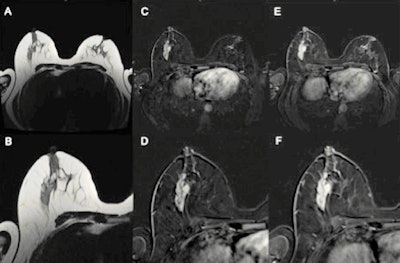

The aim of the researchers was to evaluate the diagnostic performance of untrained residents using the Kaiser Score compared with offsite radiologists experienced in breast imaging using only MR BI-RADS. Three offsite, board-certified radiologists experienced in breast imaging interpreted MRI scans according to the MR BI-RADS scale.

The same studies were read by three residents in radiology without prior training in breast imaging using the Kaiser score. All readers were blinded to clinical information, and histology was used as the gold standard.

A total of 80 women (median age, 52 years) with 93 lesions (32 benign, 61 malignant) were included in the study. The individual within-group performance of the three expert readers (area under curve [AUC], 0.723-0.742), as well as the three residents, was equal (AUC, 0.842-0.928). But the rating of each resident using the Kaiser score significantly outperformed the experts' ratings using the MR BI-RADS scale.